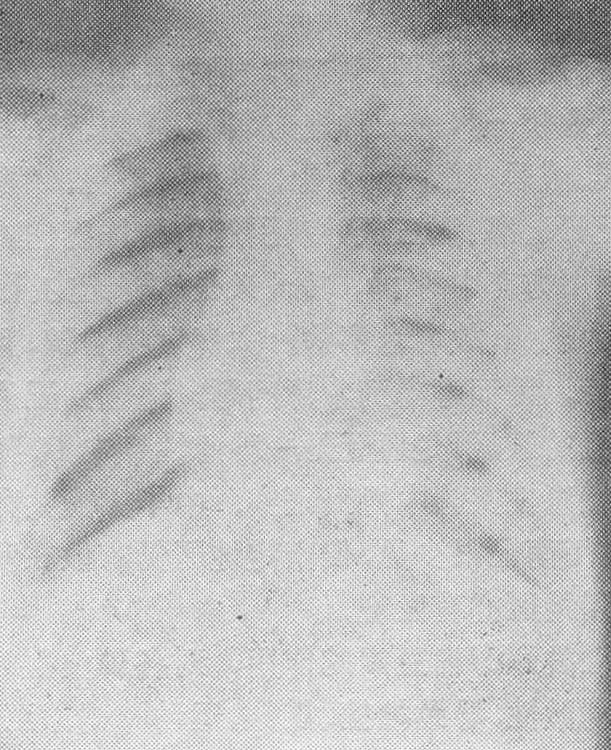

图2 氟骨症胸部X线片肋骨骨质明显致密硬化,肌肉韧带附着处有钙化

(1) 骨质硬化: 骨质硬化是氟骨症最常见的骨质变化。早期,骨小梁交叉点的骨质增多,形成砂砾状骨纹理。骨小梁普遍增粗,小梁间隙变窄,形成粗密的骨纹,进而融合成致密骨斑,直至大片骨质融合,使骨胳硬化,呈大理石样。骨膜的增生、骨化,使骨皮质增厚、髓腔变窄(图2)。四肢骨的骨外膜增生化骨后,其表层形成密质骨,下层为松质骨,于是在X线上显示出双层皮质,称为 “双框症”。腕骨和儿童跖、跗骨的骨纹粗大,也有重要诊断价值。重症患者,颅骨的内、外板增厚,板障不清或消失,颅底骨质增生 、硬化。